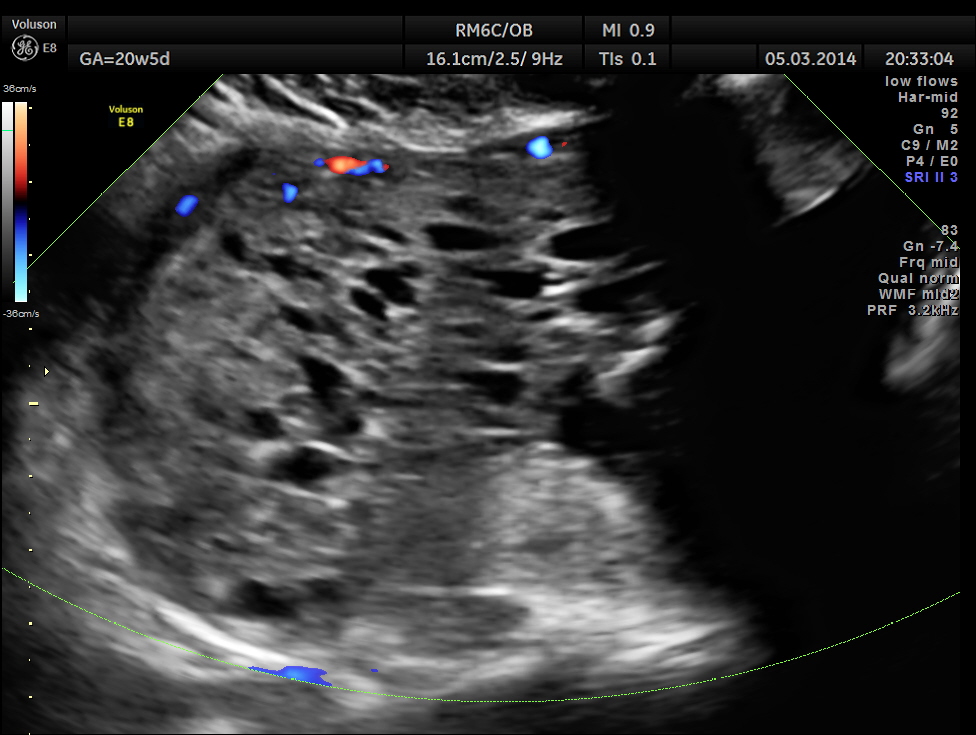

The placenta was on the anterior wall and the scan showed a distinct mass lesion in the antero right lateral portion. The placenta had multiple small cystic appearance in the right lateral aspect . Colour doppler showed no increased vascularity.